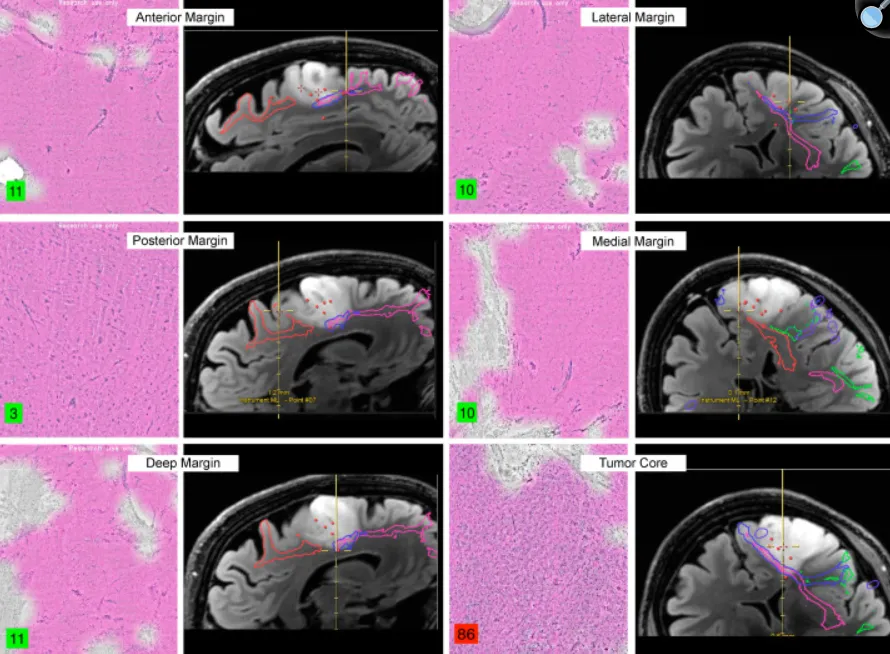

一项发表在《World Neurosurg》的研究给出了一个颠覆认知的结论:...

更新时间:2026-04-08 17:29:19

胶质瘤能不能安全切干净是很多患者担心的问题。因为,胶质瘤...

更新时间:2026-04-07 11:24:39